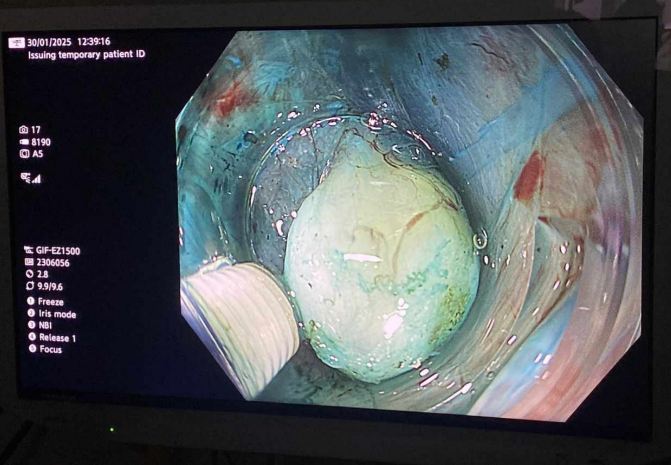

نجحت وحدة المناظير بكلية الطب جامعة حلوان في إجراء أول عملية من نوعها باستخدام منظار الموجات فوق الصوتية لتشخيص واستئصال ورم بالمريء في جلسة واحدة، دون الحاجة لإجراء فتحات جراحية، وذلك بمستشفى بدر الجامعي.

وتمت العملية في غضون 30 دقيقة باستخدام تقنية مناظير الفراغ الثالث، حيث تم تحديد نوع الورم ومكانه وحجمه ومنشئه عبر منظار الموجات فوق الصوتية، ثم استئصاله مباشرة في نفس الجلسة.

أجريت العملية تحت إشراف الدكتور شريف البحيري، مدرس الباطنة العامة بكلية الطب واستشاري المناظير التداخلية ومناظير الفراغ الثالث، والذي تلقى تدريباً متخصصاً على هذه التقنية المتقدمة في جامعة كاتب أتاتورك بتركيا خلال مهمة علمية من جامعة حلوان.